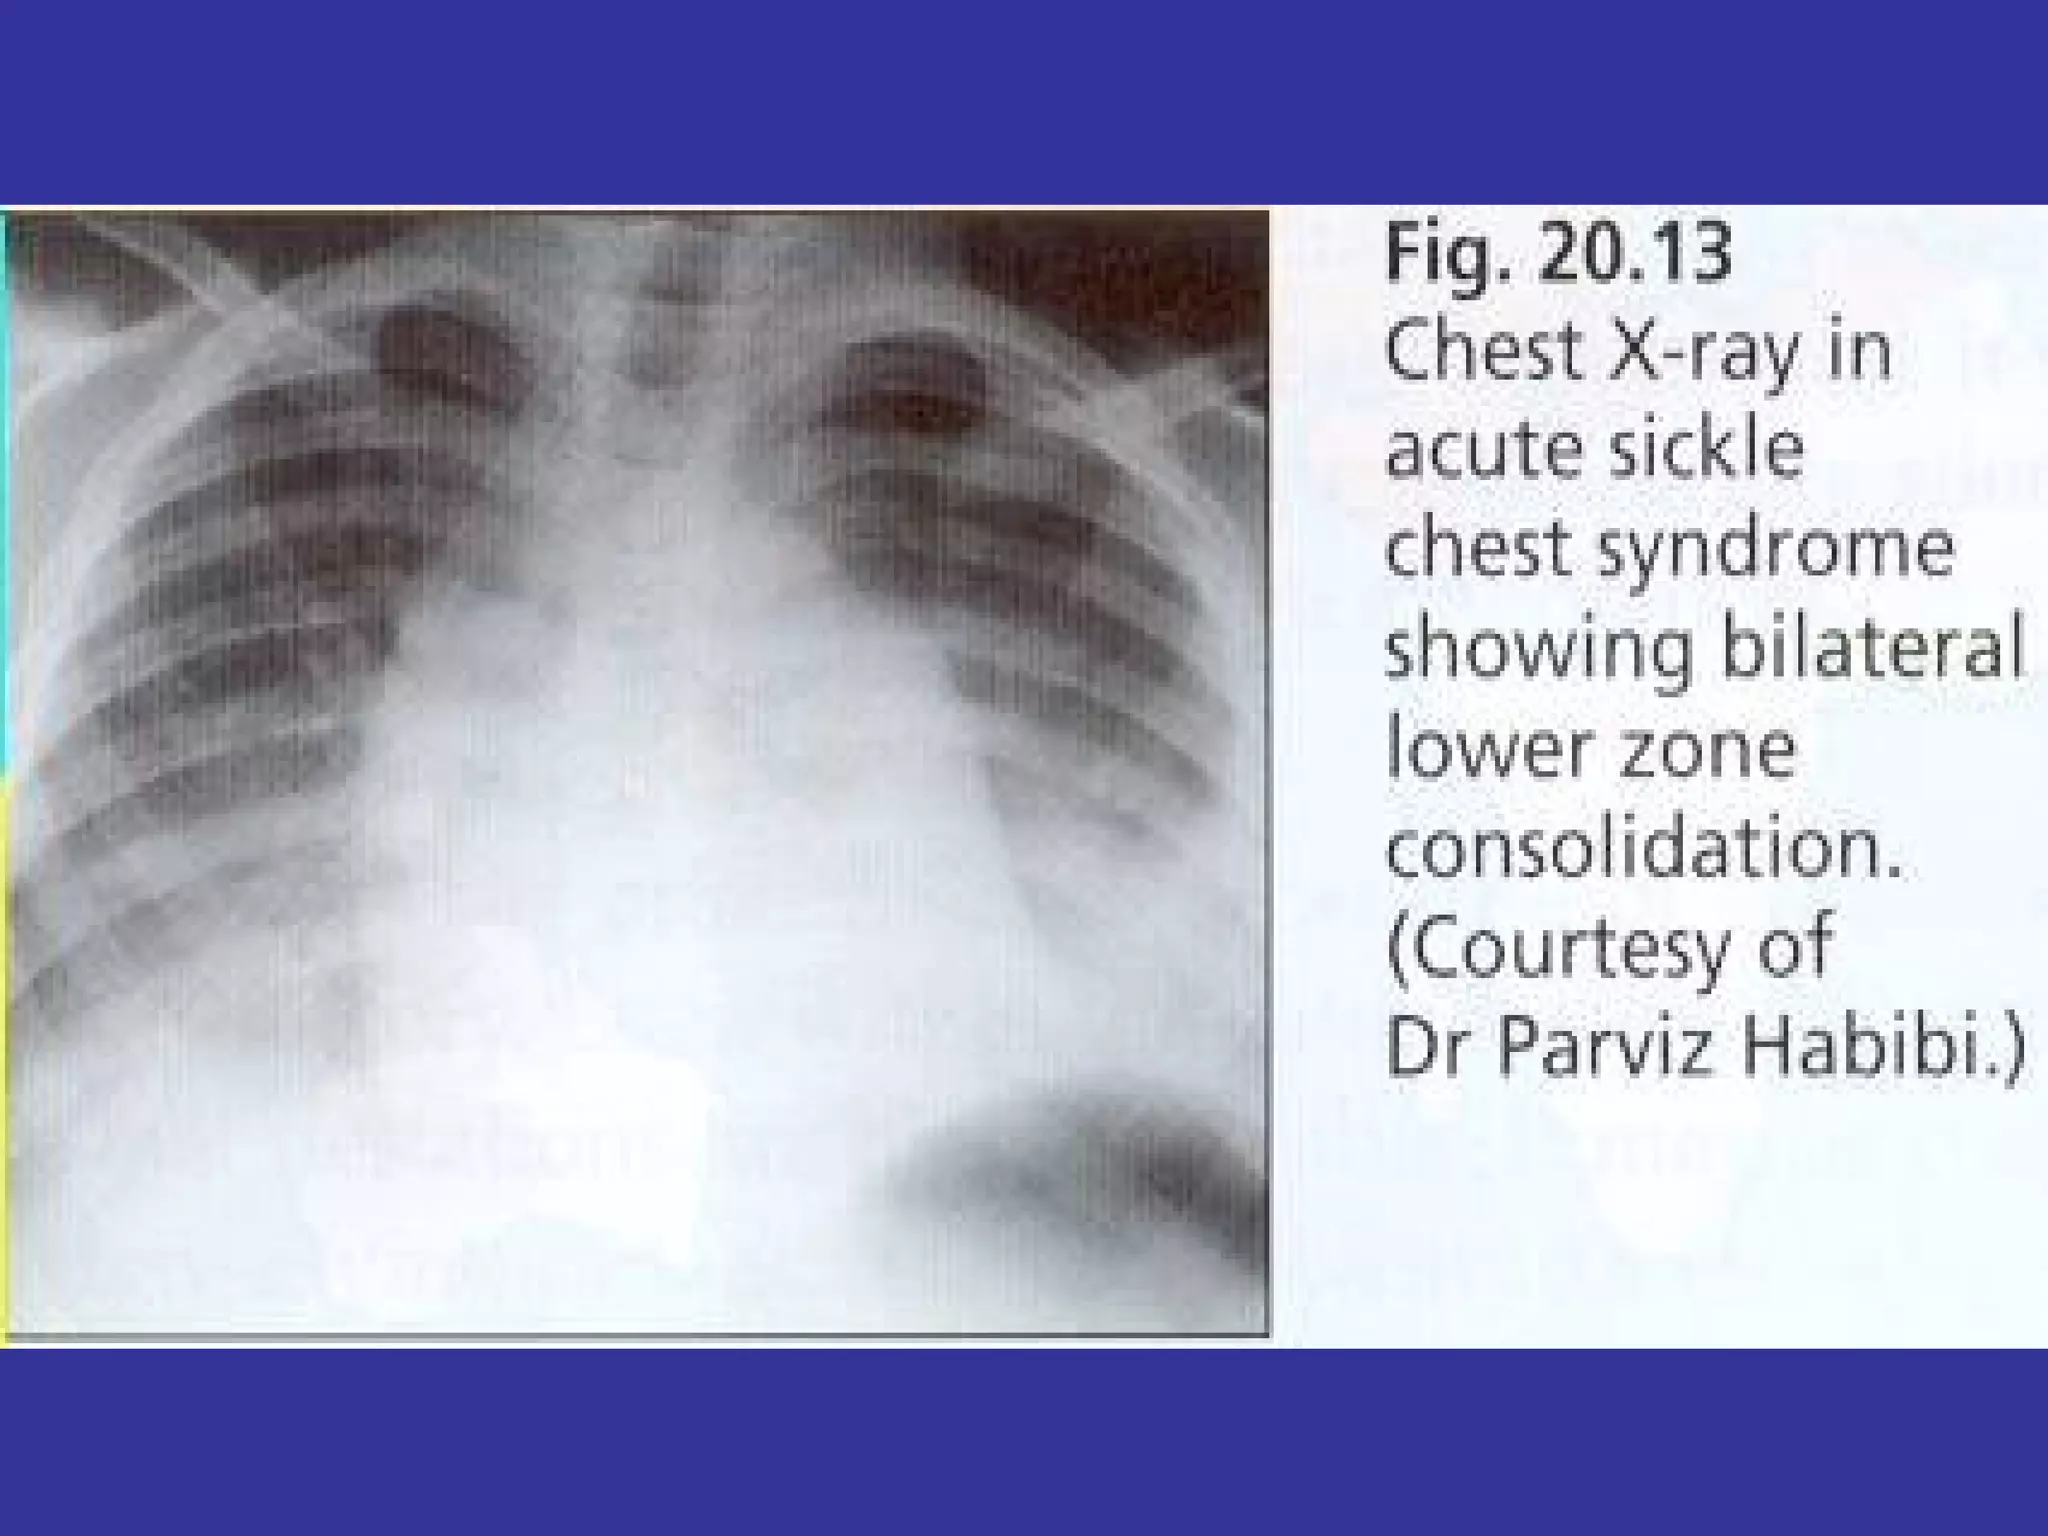

Acute Chest Syndrome (Pneumonia): - Seen in more than 50% of Sickle cell patients.  -Leading cause of mortality in sickle Cell disease Sepsis: Younger children:  S. pneumoniae  Older  children:  G-/Salmonella Symptoms :  Fever, Cough, Chest/Back pain Tachypnea, ↑ RR, Flaring, Grunting, Hypoxemia  Infiltrates in X-ray.  Treat with antibiotics Painful Vaso-Occlusive crises:   Pain in large joints, muscle, abd. pain, back pain, knee, shoulder, elbow.  Priapism Seen in children after the age of 3-4 years Swelling, tenderness, decrease of ROM at site of pain. Pain triggers:  stress, infection, menses, trauma, change of weather.  Aplastic Crisis:  Decrease of RBC production due to decrease of Hb/Retic Count.  Parvovirus B-19 (mc)  Anemia (hemolysis), Fatigue, pallor, decrease retic.  Other Ds:   Meningitis, Osteomyelitis (Salmonella), Sepsis (mcc-death)

Acute Chest Syndrome(Pneumonia): - Seen in more than 50% of Sickle cell patients. -Leading cause of mortality in sickle Cell disease Sepsis: Younger children: S. pneumoniae Older children: G-/Salmonella Symptoms : Fever, Cough, Chest/Back pain Tachypnea, ↑ RR, Flaring, Grunting, Hypoxemia Infiltrates in X-ray. Treat with antibiotics Painful Vaso-Occlusive crises: Pain in large joints, muscle, abd. pain, back pain, knee, shoulder, elbow. Priapism Seen in children after the age of 3-4 years Swelling, tenderness, decrease of ROM at site of pain. Pain triggers: stress, infection, menses, trauma, change of weather. Aplastic Crisis: Decrease of RBC production due to decrease of Hb/Retic Count. Parvovirus B-19 (mc) Anemia (hemolysis), Fatigue, pallor, decrease retic. Other Ds: Meningitis, Osteomyelitis (Salmonella), Sepsis (mcc-death)